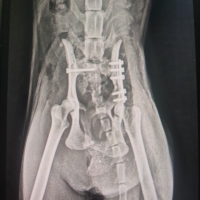

29 Ocak’ta mahallemizde baktığımız sokak kedimize bir araç çarptı. Onu arka ayaklarını sürürken bulduk. Ertesi gün acil olarak ameliyata alındı; operasyon başarılı geçti ve bacağı plakla sabitlendi. Ancak sinir hasarı olduğu söylendi. Bu süreçte klinikte, kafeste kaldı.

Geçen hafta kontrol amaçlı yeniden röntgen çekildi. Ne yazık ki plak gevşemiş ve kaymış; bu nedenle revizyon ameliyatına alındı. Ameliyat teknik olarak iyi geçti fakat bu kez çok kötü bir haber aldık: Kedimiz hamileymiş.

Mevcut durumda arka bacağının birinin ampute edilmesi gerekecek ve doğum sezaryenle yapılacak. Planlanan süreç, önce sezaryen, ardından amputasyon şeklinde ilerleyecek tek narkozla olması açısından.